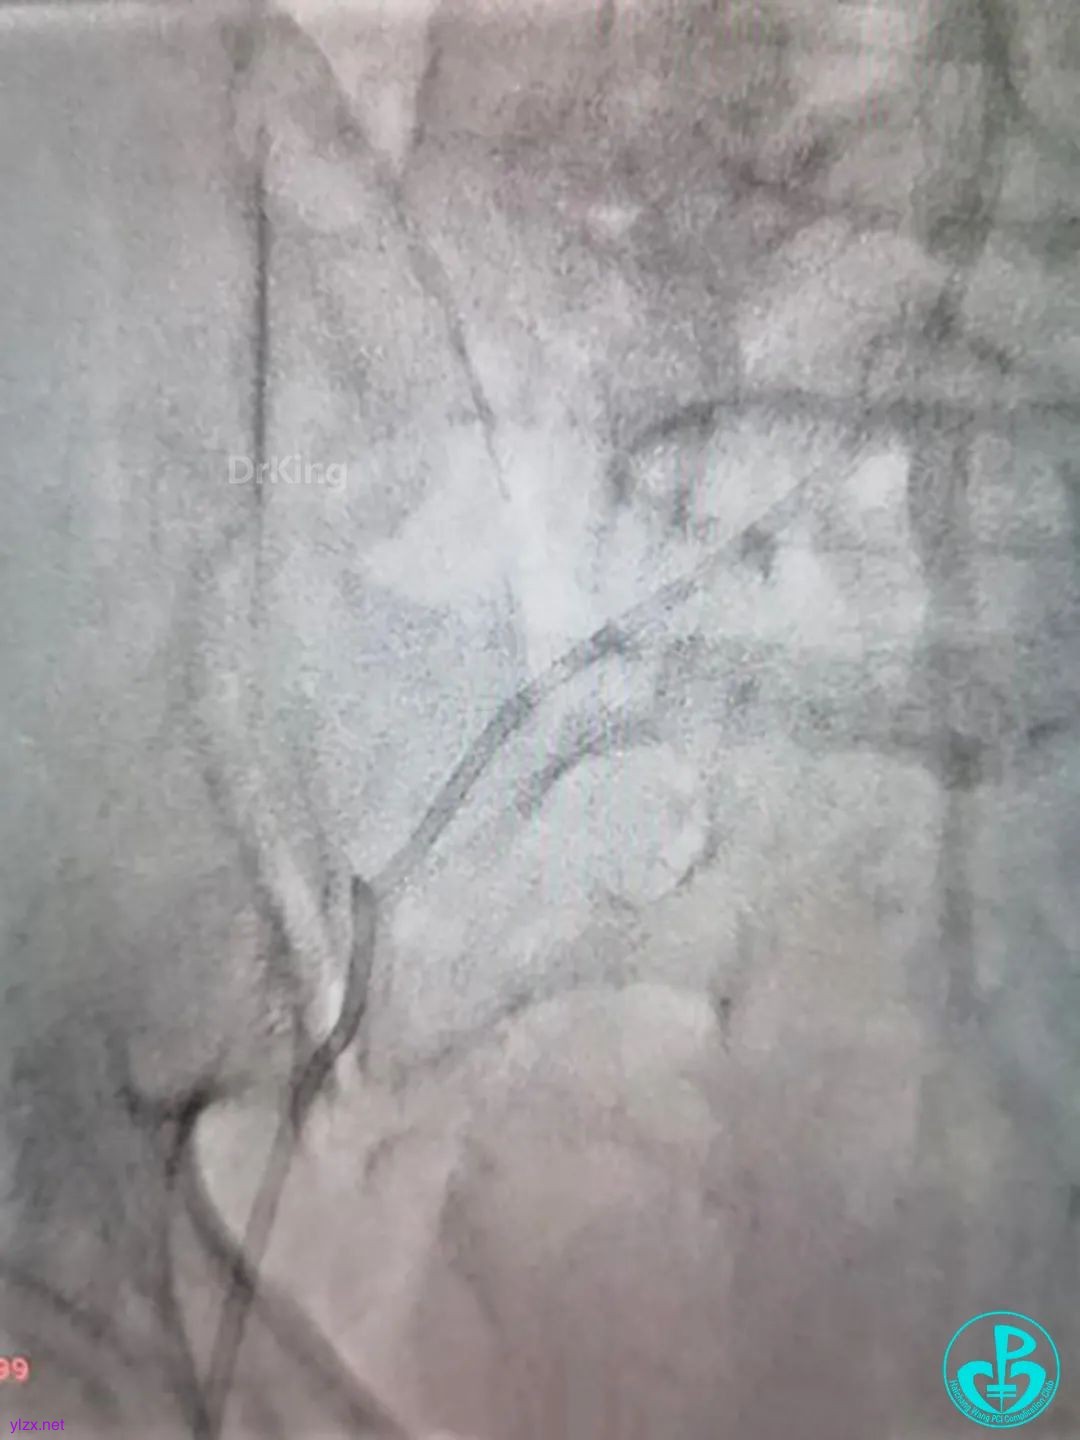

走左边,终于到位,造影。

左边EBU。

简单处理。

血运重建完成,胸痛缓解。生命体征平稳!

ACT:395s。